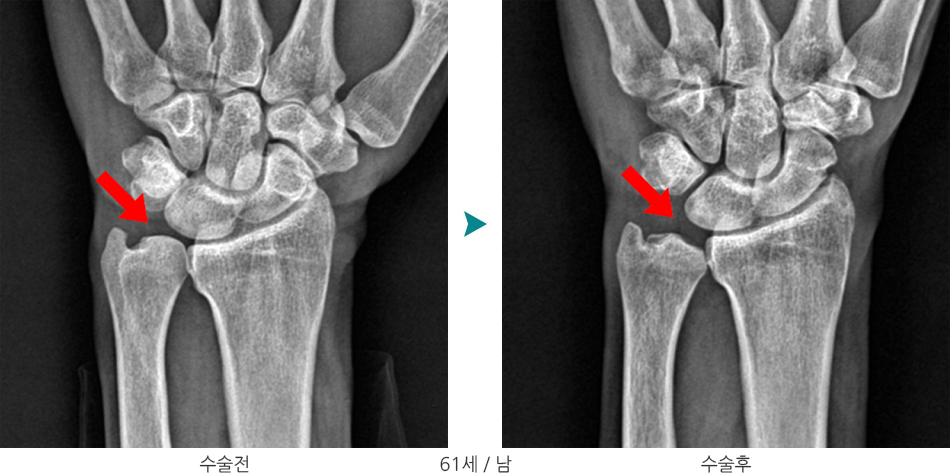

원위척골절제술 + 월상골 괴사부 변연절제술 및 미세절골술

관절경하 월상골 미세절골술 수술부위 전·후 비교